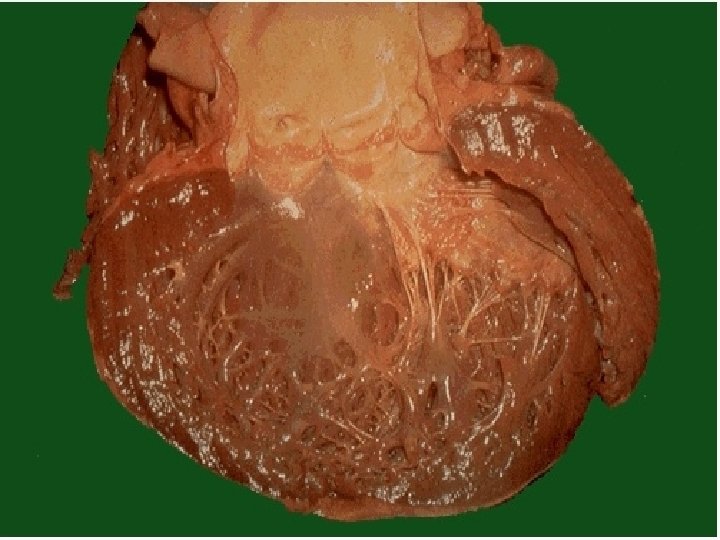

DISFUNCIÓN SISTÓLICA: Disminución de la función de bomba, o de la contractilidad del miocardio, con disminución de la fracción de expulsión (< 50%). Se ausculta un S 3. Etiología: Sobrecarga de trabajo, sea de presión o de volumen: Ejs: Cardiomiopatía dilatada, Cardiopatía Isquémica, Hipertensión, Valvulopatías.

DISFUNCIÓN DIASTÓLICA: Trastorno en la relajación con llenado anormal que produce congestión pulmonar y disminución del volumen sistólico, por ende un volumen minuto inadecuado. Se ausculta un S 4 apical. Alteración del llenado ventricular. Etiología: Hipertensión, Cardiopatía Isquémica, Cardiomiopatía Hipertrófica, Cardiomiopatía Restrictiva